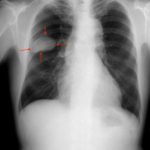

肺がん

肺がんとは、肺から発生したがんの総称です。

特に高齢の男性では、がんのなかでも最も発生頻度が高く、日本では第1位です。